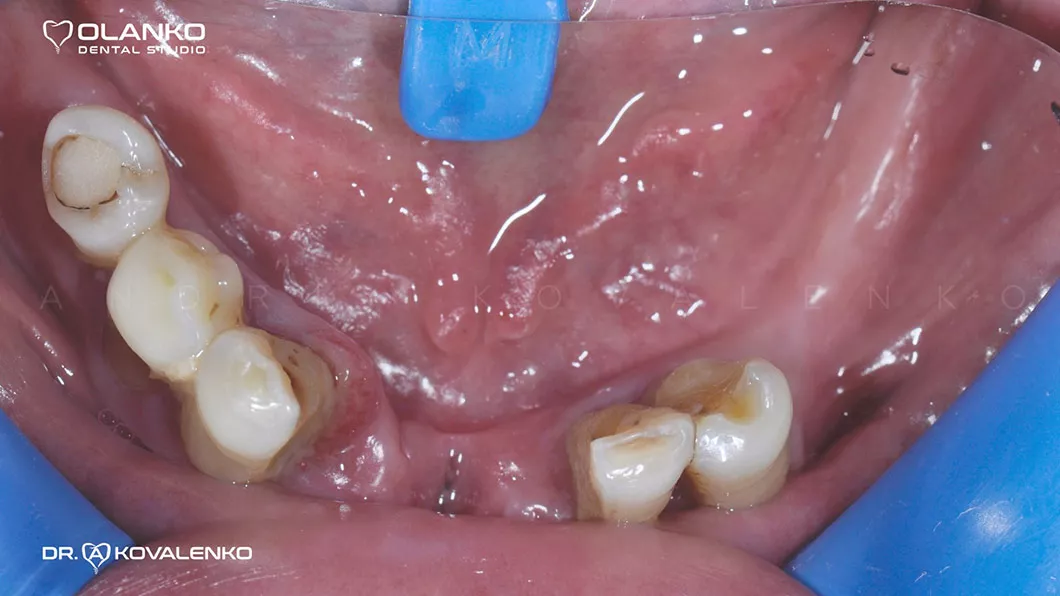

Ситуация до:

Клинический случай 1 имплантация зубов